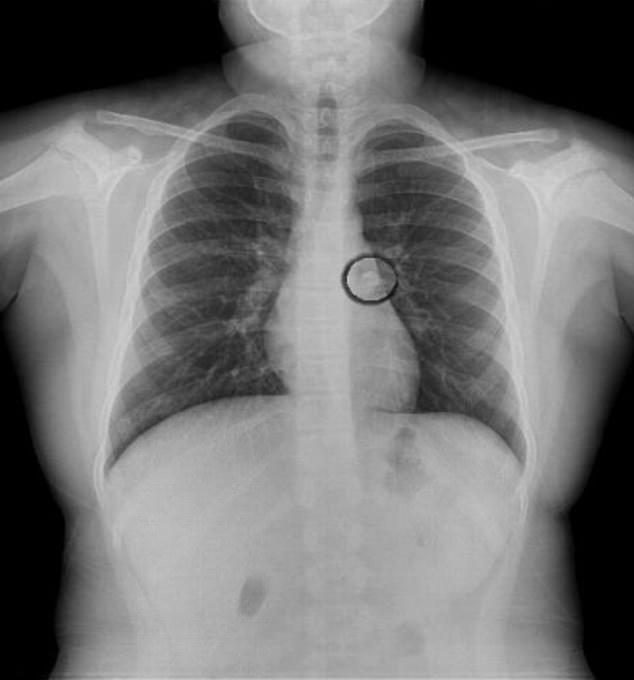

نجت طفلة تبلغ من العمر 9 أعوام من الموت بأعجوبة، بعدما بلعت سنها وهى نائمة، الأمر الذى جعلها تخضع لعملية جراحية لاستخرج السن.

ونقلت الطفلة التى لم يكشف عن هويتها إلى احدى المستشفيات التركية، بعدما لاحظ والديها اختفاء السن من فمها، وبعد فحصها بالأشعة السينية، تبين مكان السن في مجرى الهواء المؤدي للرئة اليسرى.

وقال الطبيب المعالج لها بالمستشفى إنها محظوظة جدًا لبقائها على قيد الحياة.